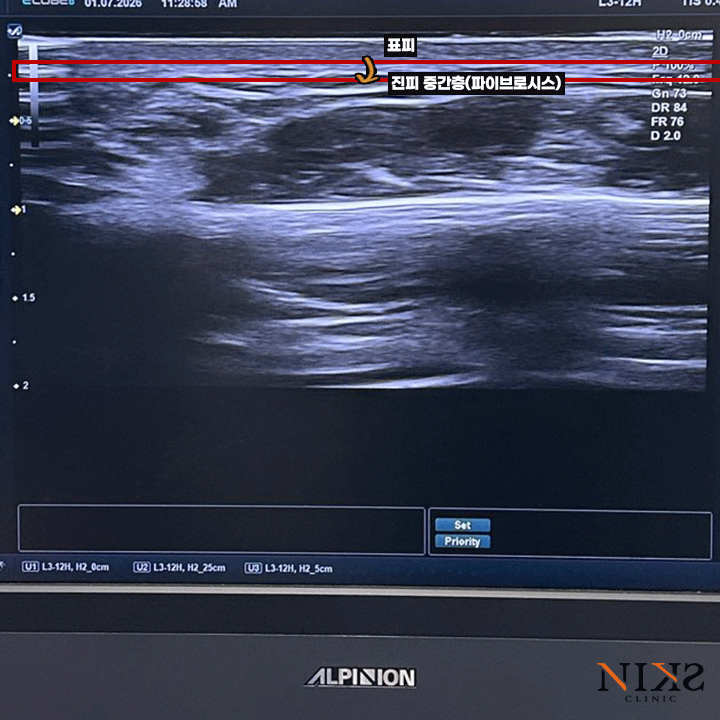

초음파 이미지로 설명드리자면

가장 윗층이(1번 부분) 피부의 표피 ~ 진피 상부,

2에서 3번 부분이 진피 중간층입니다.

그 아래쪽의 어두운 부분은 지방층인데요, 이렇게 딱 보기에도

피부와 지방 사이를 “지지하는”층이라는게 눈에 들어오죠?

이 부분이 노화되기 시작하면, 피부-지방-SMAS층 사이의 결속력이 무너지면서

피부가 늘어지고, 지방이 아래로 밀리게 되는 것입니다.

그래서 소프웨이브는 이 층을 균일하게 집중 공략해서, 피부를 아래에서 받쳐 올려주면서

피부의 밀착감을 좋아지게 만드는 것이죠.